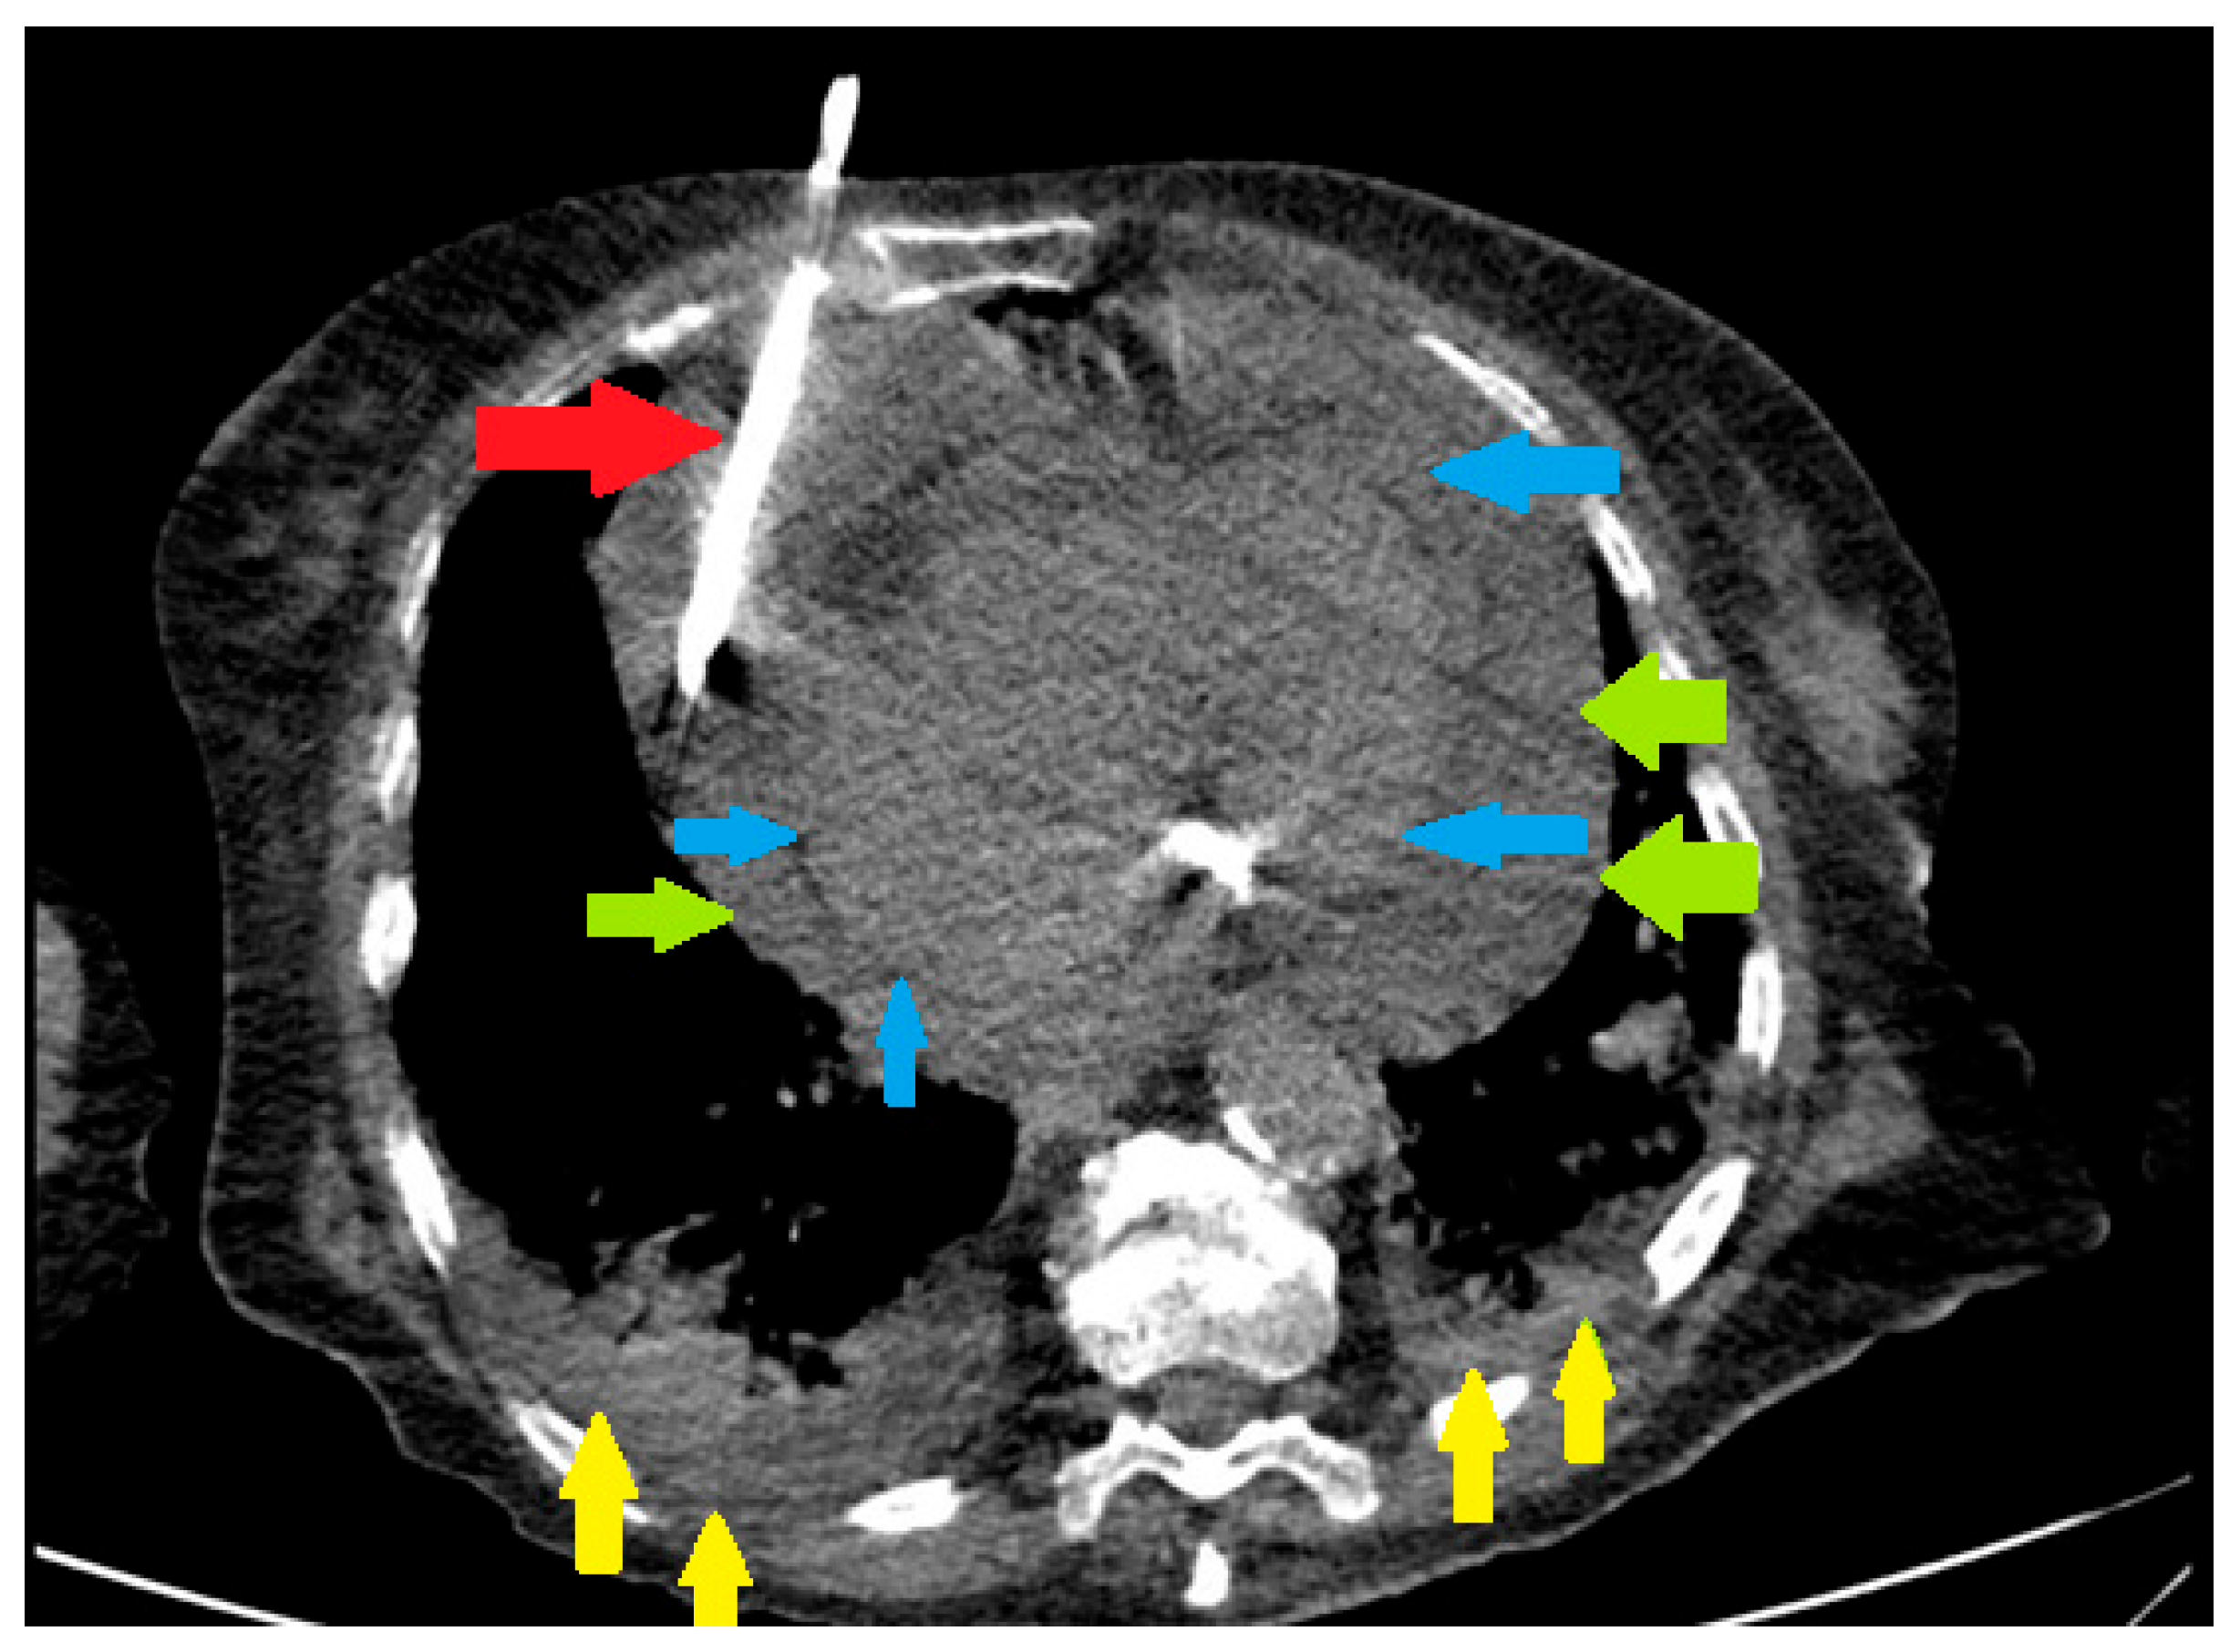

Pericardiocentesis was defined as needle aspiration of pericardial fluid or any surgical procedure involving drainage of pericardial fluid, including surgical pericardiotomy and pericardial window (Figure 1). Patient records with ICD code of pericardiocentesis, pericardiotomy or pericardiectomy were thoroughly reviewed by the investigators, to ensure that drainage of pericardial fluid was performed.

Figure 1. Pericardial drain insertion in a patient with COVID-19 infection, large pericardial effusion and bilateral pneumonia. Red arrow – pericardial drain. Green arrows – parietal pericardium. Blue arrows – visceral pericardium. Yellow arrows – pulmonary infiltrate.